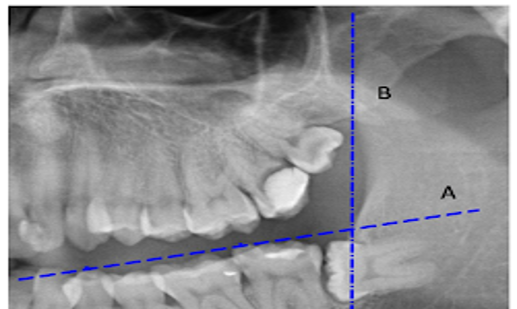

The image is a panoramic radiograph showing a mandibular fracture. What type of fracture is most likely depicted, and what treatment approach would be appropriate?

What radiographic feature is seen, and what does it indicate about the impacted tooth?